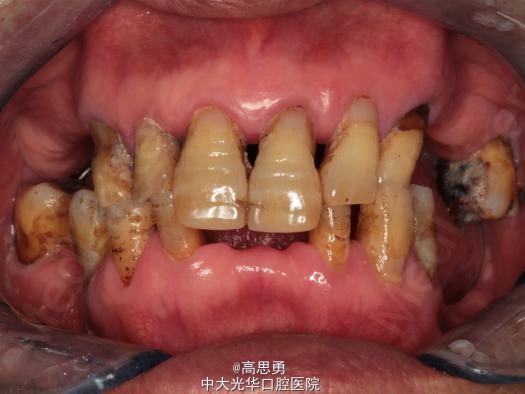

检查(包括专科检查及辅助检查): 1、全身状况良好,无全身系统性疾病,自主行动能力正常。精神心理状态无异常。 2、颌面部左右对称,面部比例协调,面部正面形态尖圆形。颞下颌关节运动无异常,开口型无异常,颞下颌关节无弹性,无压痛。 3、口内黏膜未见瘢痕,舌运动无异常。唇颊系带附着无异常,唾液分泌无异常。 4、牙龈正常,无肿胀无瘘管。 5、口内检查: #32近中移位约1mm,无明显倾斜 #44远中移位约2mm,向缺隙侧倾斜,伸长约1mm 其余缺牙间隙正常 全口牙龈退缩至根颈1/3,牙龈无肿胀无瘘管 上颌缺牙区牙槽嵴无明显吸收、下颌缺牙区牙槽嵴吸收呈低平刃状 口腔卫生状况欠佳、全口牙石多 11 12 13 14 15 16 17 21 22 23 24 25 26 27 视 存 存 存 缺 缺 缺 缺 存 存 存 缺 缺 缺 存 探 - - + - - - - - - - - - - - 叩 - - + - - - - - - - - - - - 松 - - I° - - - - - - - - - - - 楔 O O O - - - - O O O - - - - 31 32 33 34 35 36 37 41 42 43 44 45 46 47 视 缺 存 存 存 缺 缺 缺 缺 存 存 存 缺 缺 存 探 - - - - - - - - - - - - - - 叩 - - - - - - - - - - - - - - 松 - - - - - - - - - - - - - - 楔 - - O - - - - - O O O - - - 根尖X片示:13 根尖部阴影,牙颈部硬组织部分缺损 转诊牙体牙髓科后复诊 修复科第二次就诊口内检查: 11、12、13、21、22、23、33、42、43、44牙颈部见黄色充填物 13 探(-)、叩(-)、松(-),HE面见白色暂封物 口腔卫生状况尚可、牙石少,其余牙叩(-)、松(-) 根尖X片示:13 根尖部阴影,根充可 其余同前

诊断: 1、牙列缺损(上颌肯氏II类I分类,下颌肯氏II类II分类) 2、#13慢性根尖周炎 3、#11、#12、#13、#21、#22、#23、#33、#42、#43、#44楔状缺损 4、慢性牙周炎 治疗计划 1、#13转牙体牙髓科做RCT 2、转牙体牙髓科对#11、#12、#13、#21、#22、#23、#33、#42、#43、#44楔状缺损 充填治疗 3、转牙周科进行牙周洁治 4、择期RPD修复 备选修复方案: 1、#13RCT后截冠后,上下颌覆盖义齿修复; 2、#13RCT后冠修复,上下颌可摘局部义齿修复; 3、#13RCT后树脂充填,上下颌可摘局部义齿修复; 4、#13拔除后,上下颌可摘局部义齿修复。 患者意愿:患者希望尽量保持#13的天然形态,要求费用尽量低,但能恢复正常咀嚼功能。 最终治疗方案:根据患者的年龄、身体状况、治疗周期、经济状况,患者最终选择方案5,即#13RCT后树脂充填,上颌结合卡环式可摘局部义齿修复;下颌可摘铸造支架式局部义齿修复。 治疗过程: 1、临床检查和#13树脂充填 对患者进行全面的口腔检查,用Z350树脂充填#13,调HE,抛光。 2、研究模型 调拌藻酸盐印模材料于2号成品托盘上取上下颌研究模,灌注石膏模型,研究分析、制定治疗计划,并制作个别托盘。 3、基牙预备 对#13近中、#23远中、#27近中、#34近中、#47近中常规制备支托凹,抛光。 4、工作模型 调拌藻酸盐印模材料于个别托盘上。做一定的边缘整塑,取上下颌研究模,灌注石膏模型。 5、试戴支架 检查支架的就位、固位可,无翘动,调HE,抛光,用蜡堤取颌位关系,上颌架,排牙,比色C4。 6、试排牙 检查义齿的就位、固位可,无翘动,观察人工牙的咬合状况,尖窝接触良好,正中颌位能重复,患者无诉不适,面容自然,外观满意。送加工厂充胶制作最终修复体。 7、试戴 检查义齿的就位、固位可,无翘动,咬合关系正确,利用咬合纸检查,上下颌尖窝接触均匀全面,抛光,患者表示满意,嘱注意事项,定期复诊。